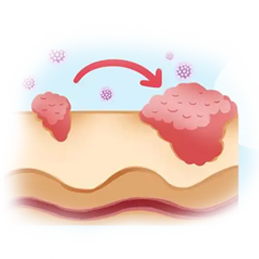

ΤΛΖτΑ© «“Μ÷÷≥ΘΦϊΒΡΕώ–‘÷ΉΝωΘ§”…ΤΛΖτœΗΑϊ“λ≥Θ‘ω…ζΥυ“ΐΤπΘ§÷ς“ΣΖ÷ΈΣ»ΐ÷÷άύ–ΆΘΚΜυΒΉœΗΑϊΑ©Θ®BCCΘ©ΓΔΝέΉ¥œΗΑϊΑ©Θ®SCCΘ©ΚΆΚΎ…ΪΥΊΝωΘ®MelanomaΘ©ΓΘΝΥΫβΤδ≤Γ“ρΓΔ‘γΤΎ÷ΔΉ¥ΦΑΖά÷ΈΖΫΖ®Θ§”–÷ζ”ΎΗϋΚΟΒΊ±ΘΜΛΤΛΖτΫΓΩΒΓΘ

ΚΎ…ΪΥΊΝωΘ®MelanomaΘ© «“Μ÷÷‘¥”ΎΤΛΖτ÷–ΚΎ…ΪΥΊœΗΑϊΒΡΑ©÷ΔΓΘΚΎ…ΪΥΊœΗΑϊΗΚ‘π≤ζ…ζΚΎ…ΪΥΊΘ§’β÷÷Έο÷ ΈΣΤΛΖτΓΔΆΖΖΔΚΆ―έΨΠΧαΙ©―’…ΪΓΘΨΓΙήΚΎ…ΪΥΊΝωΉν≥ΘΦϊ”ΎΤΛΖτΘ§ΒΪΥϋ“≤Ω…“‘‘Ύ―έΨΠΓΔΩΎ«ΜΓΔ≥ΠΒά…θ÷ΝΤδΥϊ≤ΩΈΜ≥ωœ÷ΓΘ